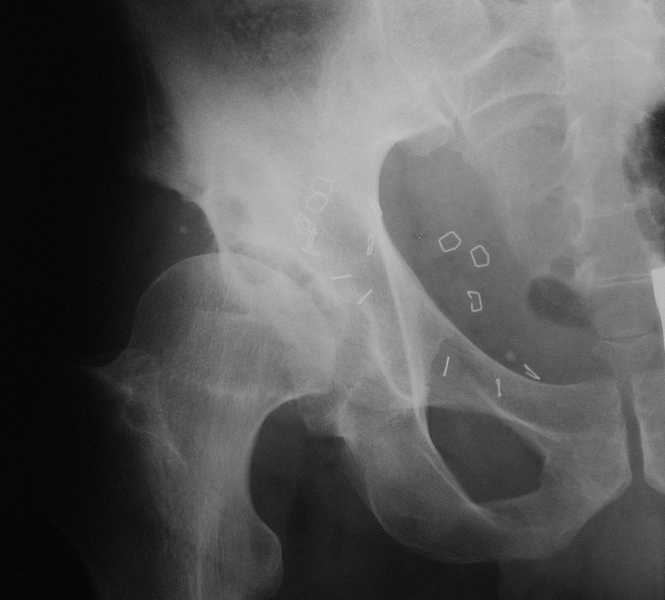

Для установки диагноза достаточно информации, на рентгенограмме передний и задний край ацетабулум образовали перекрест, "цифру восемь", указывающий на небольшую ретроверсию, а суставная щель одинаковой ширины на всем протяжении, что доказывает, что с покрытием хряща проблем нет. Головка бедра покрыта всего наполовину, это явное нарушения взаимоотношений.

Неоднократные обсуждения на форуме "пропущенных переломов" показывает, что короткие урезанные снимки приводят к ошибке, тем более у данного больного для решения тактики лечения необходимо детальное исследование суставов.

А для данного случая, необходим прямой снимок таза с отдельными суставами, также включить боковые снимки сустава, немаловажно знание покрытия головки спереди.